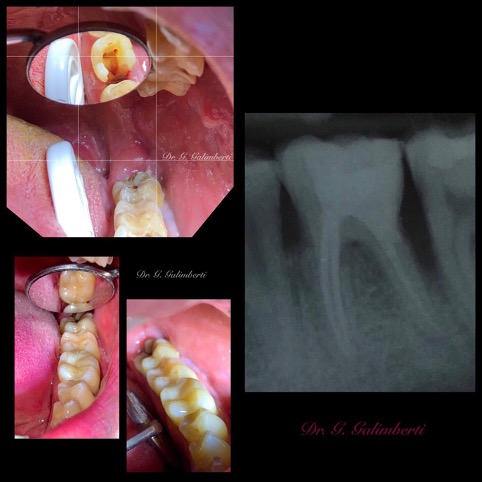

Una corretta terapia canalare con un perfetto sigillo a livello degli apici delle radici è fondamentale. I denti devitalizzati impropriamente possono creare ulteriori problemi che poi andranno a ripercuotersi sulle cure effettuate successivamente come le ricostruzioni e le corone protesiche con conseguente fallimento del piano terapeutico.

Capita spesso di incontrare denti già devitalizzati in maniera impropria che necessitano, seppur asintomatici, di essere ritrattati per evitare che i granulomi infetti visibili radiograficamente si evolvano riassorbendo tutto l’osso sottostante.

Un adeguata endondonzia serve per salvare quei denti che altrimenti sarebbero destinati ad essere estratti. Quando un dente viene devitalizzato viene privato della sua irrorazione sanguigna e del nutrimento, rendendo la sua struttura più “vetrosa” quindi più fragile e soggetta a fratture. Per questo motivo è consigliabile nella maggior parte dei casi capsulare i denti una volta che hanno perso la loro vitalità.